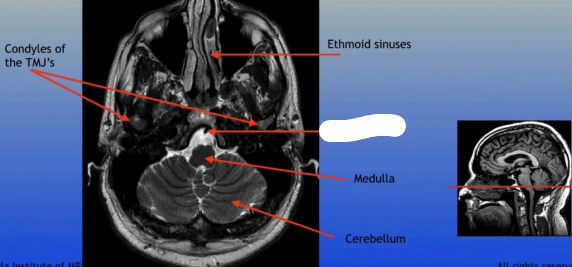

Condyles of the TMJ

Ethmoid Sinuses

Medulla

Cerebellum